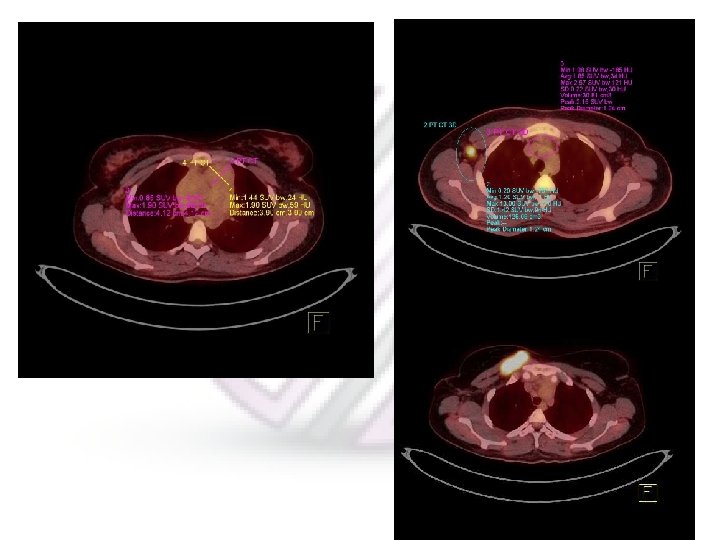

Progressive Disease A 29 Y/O lady with Hodgkin’s lymphoma; status post CTX, completed 2 weeks before PET. She is referred for restaging after therapy. 5 months later

Partial Metabolic Response Left: The patient is a case of biopsy proven diffuse large B cell lymphoma and referred for staging. Right: Monitoring response 17 days after completion chemotherapy

The previously seen, intensely FDG avid, huge retroperitoneal, conglomerate lymphadenopathy is significantly reduced in size (with a small residual remnant) and FDG uptake (SUVmax = 3. 2; prior = 27. 0). However, the uptake in residual mass is mildly greater than the liver (SUVmax = 2. 9) on the current study.